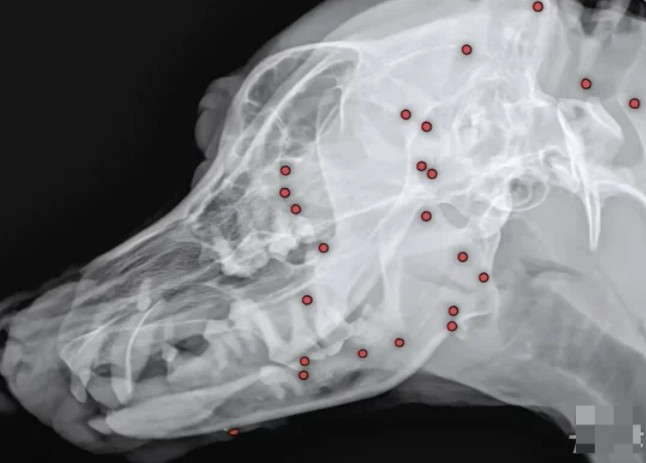

온몸에 수십개 총알이 박힌 채 돌아다니던 백구가 구조돼 안쓰러움을 사고 있다.

24일 VIP동물의료센터 성북점에 따르면 백구는 최근 도그어스플래닛에서 구조 후 해외 입양을 준비하던 중 건강검진을 했다가 충격적인 결과를 확인했다.

백구의 몸에 70개가 넘는 산탄총 파편이 박혀 있었던 것이다.

백구의 몸에 70개가 넘는 산탄총 파편이 박혀 있었던 것이다. 동물병원에서는 엑스레이, CT(컴퓨터단층촬영) 등 정밀검사에 들어갔다.

안승엽 VIP동물의료센터 원장은 “총알이 머리 쪽부터 어깨, 가슴통, 엉덩이, 다리까지 너무 많이 있었다”며 “살아있는 게 기적”이라고 말했다.

안 원장은 “70여 개 탄알을 한번에 다 제거하기는 현실적으로 어려워 백구의 얼굴을 위주로 최대한 많이 제거하는 방향을 선택했다”면서 “그렇게 26개의 파편을 제거했다”고 설명했다.